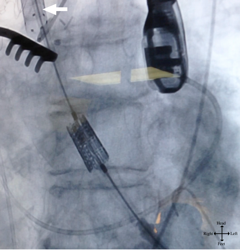

The graft was punctured with an 18 gauge needle followed by a 6F arterial sheath. A Kumpe catheter and straight wire were used to cross the aortic annulus. The straight wire was then exchanged for an Amplatz stiff wire, curved to fit the ventricle. After the Kumpe catheter was removed, an Ascendra delivery system was secured to the graft (Figure 3). Balloon valvuloplasty was then performed using a 23 mm balloon, followed by delivery of a 26 mm Sapien valve across the aortic annulus (Figure 4). Under rapid pacing, the valve was deployed. Transesophageal echocardiogram revealed a well-seated valve with trace perivalvular leakage. The Ascendra delivery system was then removed, and the graft was amputated proximal to the puncture site with clips and vascular stapler. There was no evidence of aortic dissection by TEE. The thoracotomy incision was closed in standard fashion. The patient remained intubated, in NSR, hemodynamically stable. She was discharged without complications, and was alive at one-year follow-up.

Figure 4: Sheath in side-graft (Arrow). Retrograde placement of percutaneous valve in aortic annulus prior to deployment.